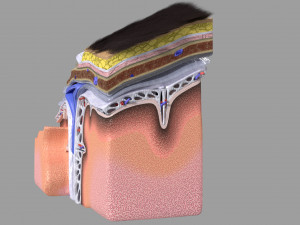

Brain with meninges scalp detailed labelled 3D 3D मॉडल

A blend model of brain along with its covering layers (meninges), skull bone and scalp labelled in detail and anatomically precise. The parts depicted are white, gray, pia, arachnoid, dura, bone, skin, fat, aponeurosis, periosteum, falx cerebri and more.

The material is high resolution image textures and normal maps based on non overlapping UVs. The texture and normal maps are packed with the blend file itself.